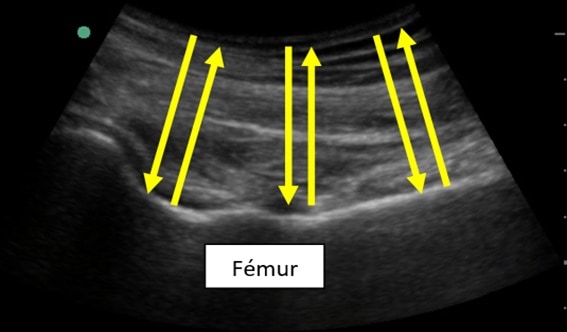

Reflexión

Si el ultrasonido atraviesa una interfase fina y amplia, con densidades diferentes, se reflejará en su mayoría, produciendo un eco de gran intensidad, como puede ocurrir al encontrar la interfase entre músculo y hueso.

En la imagen siguiente, se puede apreciar el fémur de un paciente. El ultrasonido llega hasta la interfase del hueso (muy denso) con el tejido circundante (muy poco denso) y se refleja con una intensidad alta (y por eso se muestra más “blanco” en la pantalla, como luego veremos).